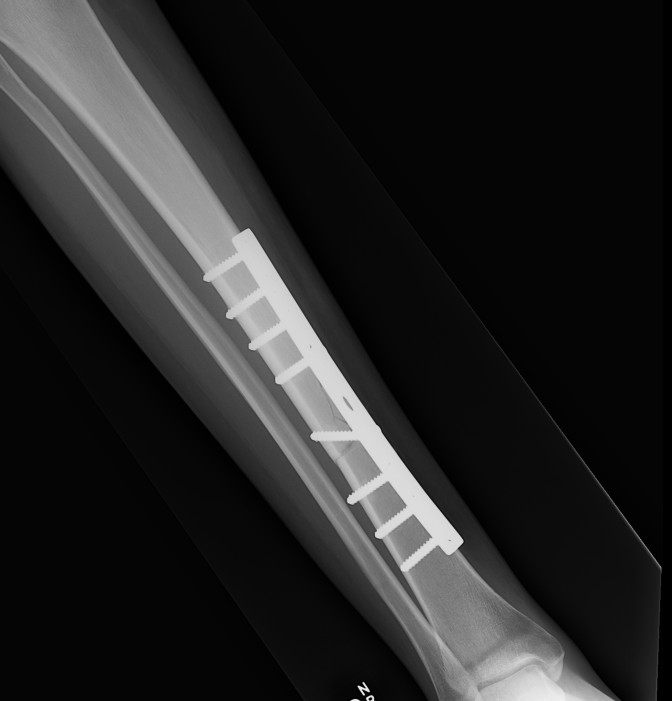

2. Plate fixation

Tibial Midshaft PlateTibial Midshaft Plate Lateral

Risk

- poor skin / blood supply / muscle cover

- excessive soft tissue stripping

Technique

- minimally invasive

- indirect reduction techniques

Results

He et al. Clinics 2014

- meta-analysis of 11 studies

- MIPO plate v IMN

- faster union rates with plate

- no increased infection or reoperation

https://www.ncbi.nlm.nih.gov/pmc/articles/PMC3971355/pdf/cln-69-04-234.pdf